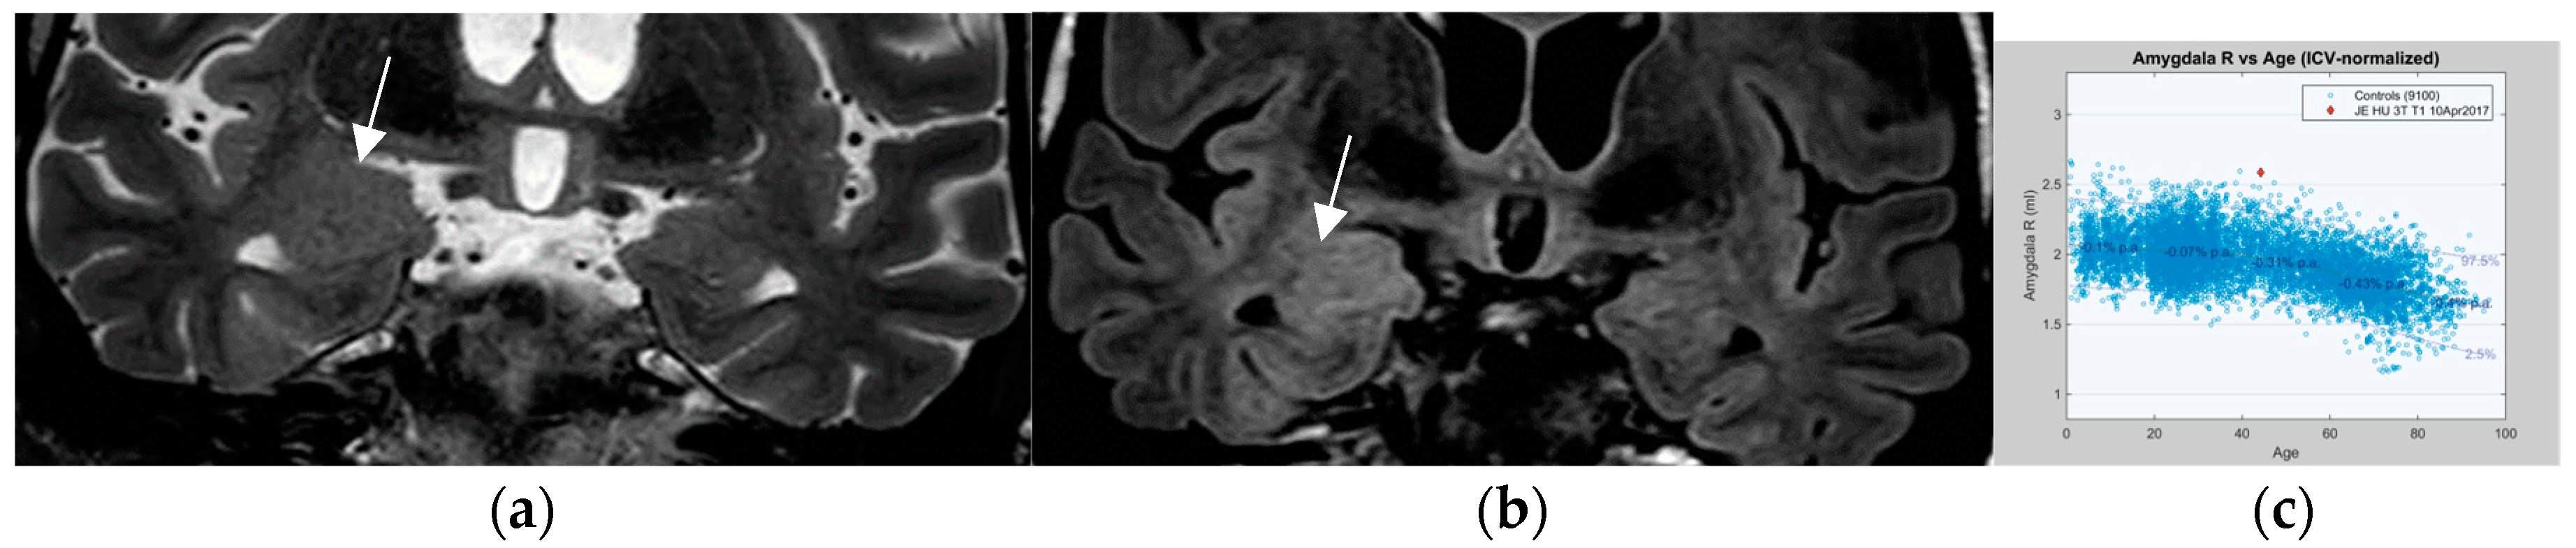

In a prior study [67] and in a recent prospective evaluation of the HARNESS protocol [68] in 123 and 131 patients, the sensitivity of MRI was particularly enhanced through interpretation by experienced readers for the diagnosis of hippocampal sclerosis and focal cortical dysplasia as the previously most frequently missed entities in adults and children, respectively. The combination of a dedicated MR and expert reader assessment increased detection of hippocampal sclerosis from 18 to 45% and of focal lesions from 50 to 91% [67]. Expert readers are more likely to recognize focal hippocampal sclerosis (Figure 2) and detect associated indirect signs such as atrophy of the ipsilateral fornix and mammillary body. Observations like the transmantle sign and subtle changes to adjacent white matter in focal cortical dysplasia and periventricular nodular and subcortical band heterotopia are challenging and less likely to be missed visually by an experienced reader.

Hippocampal sclerosis depicted on coronal FLAIR (a) and T2 w sequence (white arrows) (b) (1.7 mm each) with volume reduction of the CA1-4 regions of the left hippocampus. FLAIR and T2 signal increases and slight atrophy of the left fornix (short arrow in (b)). Marked volume reduction of left temporal lobe as evidenced by the lower position of the left Silvian fissure (long arrow in (b)) compared to the right side.

4.7. Postprocessing by Quantitative Analysis of Signal Intensity, Volumetry Enhances Temporal Lesion Identification

Coronal high resolution T2 weighted sequences and 3D Flair sequences are standard constituents of an epilepsy specific protocol to render visible hippocampal sclerosis, FCD type II, and areas of gliosis. Data postprocessing by MRI quantification relates to calculation of Flair and T2 signal (relaxometry) of the hippocampus and within lesions of the temporal lobe. Volumetry signifies quantification of the volume of the hippocampus and amygdala (Figure 7).

MR volumetry (a) and T2/FLAIR relaxometry (b): right hippocampal abnormality histologically verified as hippocampal sclerosis and gliosis as evidenced by a mild area decrease of the right hippocampus (0.78 cm2 versus 0.90 cm2) and a slight FLAIR signal elevation (245 vs. 217). Both findings were suspected visually but were verified by postprocessing of volume and signal intensity.

In 78 patients with temporal lobe epilepsy, T2 relaxometry identified lesions in an additional 15 patients (19%) with visually normal MRI and volumetry identified a further 10 cases (13%) of hippocampal sclerosis. The combination of T2 relaxometry and volumetry provided the highest yield with recognition of hippocampal sclerosis in 22 (28%) patients with previous normal interpretations [81]. However, contrary to hippocampal sclerosis, FCD type I lesions, despite postprocessing, still have a high association with MR interpretation as “nonlesional”.